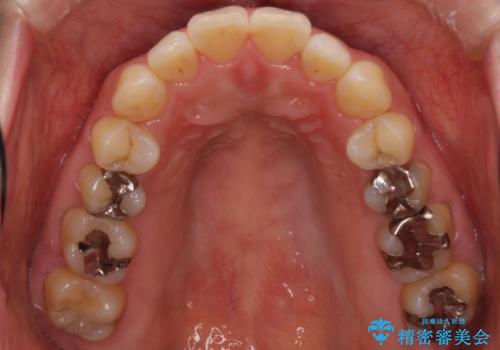

- 口が閉じずらく、口元が突出している状態でした。

上下左右の歯を1本ずつ、合計4本抜歯して、ワイヤーにて矯正することとなりました。

もともと下の前歯の永久歯が1本欠損しており、抜歯部位の選択を考慮しなければならない症例でした。シミュレーションを事前に行い、下顎の抜歯部位を決定しました。